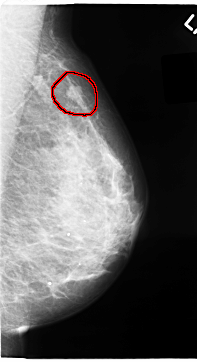

FILE: C_0065_1.LEFT_MLO.OVERLAY

TOTAL_ABNORMALITIES 1

ABNORMALITY 1

LESION_TYPE MASS SHAPE LOBULATED MARGINS MICROLOBULATED

ASSESSMENT 4

SUBTLETY 5

PATHOLOGY MALIGNANT

TOTAL_OUTLINES 1

BOUNDARY